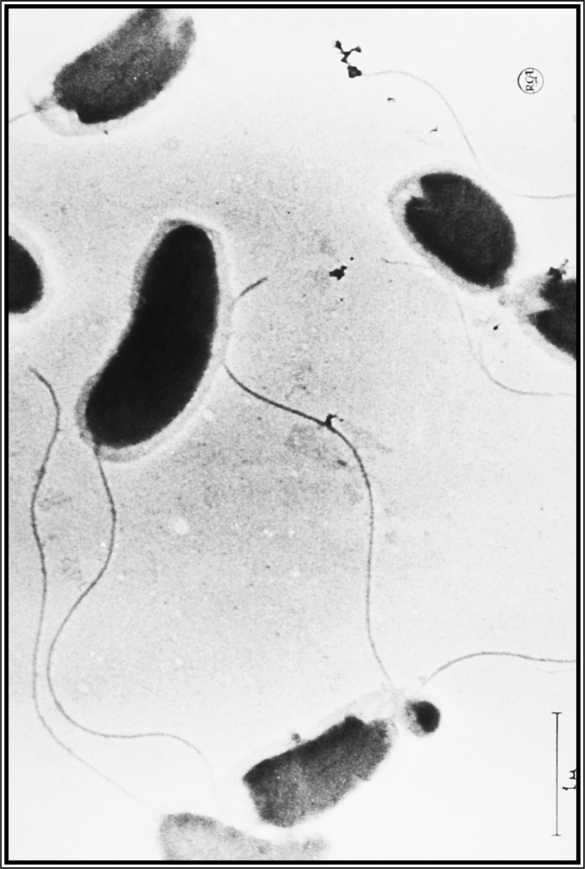

Иллюстрация к книге — Карта призраков. Как самая страшная эпидемия холеры в викторианском Лондоне изменила науку, города и современный мир [i_008.jpg]

Иллюстрация к книге — Карта призраков. Как самая страшная эпидемия холеры в викторианском Лондоне изменила науку, города и современный мир [i_009.jpg]

Холерный вибрион под микроскопом